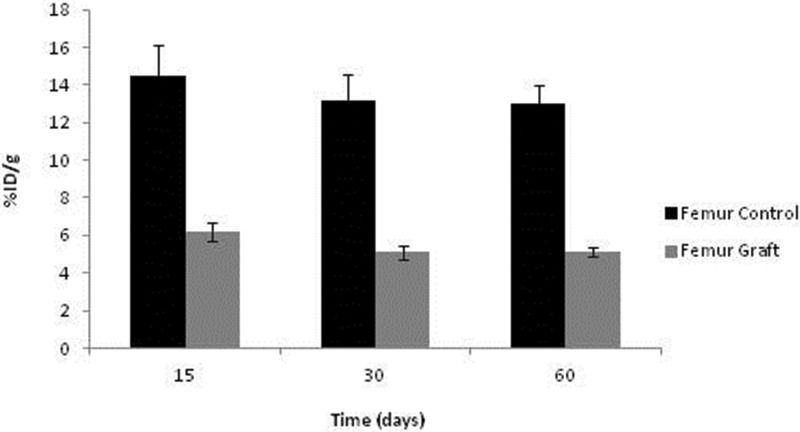

No significant differences in 99mTc-MDP were detected over time among the syngeneic implants or control femurs, although a tendency toward graft reduction at 30 and 60 days was evident. As expected, the control uptake was substantially higher than in the ischemic grafts. It should be emphasized that the avascular graft values were not negligible, indicating sustained viability and metabolic activity, as documented with 99mTc-HYNIC-E-c(RGDfK)2 (Figure 7).

RESULTS:Radiolabeling achieved high (>95%) radiochemical purity. The biodistribution confirmed good blood clearance 1 hour after administration. For 99mTc-hydrazinonicotinic acid (HYNIC)-E-[c(RGDfK)2, remarkable renal excretion was observed compared to 99mTc-methylene diphosphonate (MDP), but the latter, as expected, revealed higher bone uptake. The results obtained in the control femur were equal at all time points. In the implanted femur, 99mTc-HYNIC-E-[c(RGDfK)2 uptake was highest after 15 days, consistent with early angiogenesis. Regarding 99mTc-MDP in the implant, similar uptake was documented at all time points, consistent with sustained bone viability; however, the uptake was lower than that detected in the control femur, as confirmed by histology.